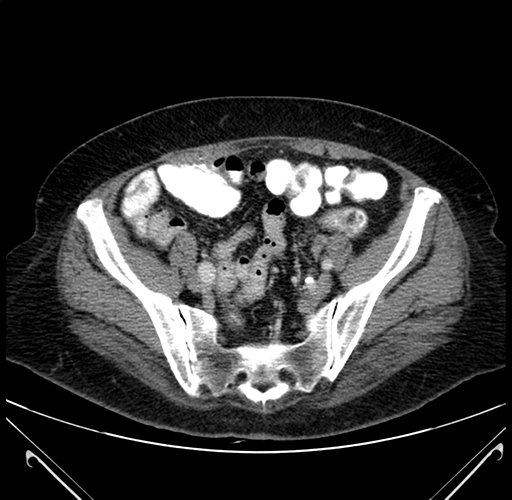

Pre-Chemo: Axial Venous